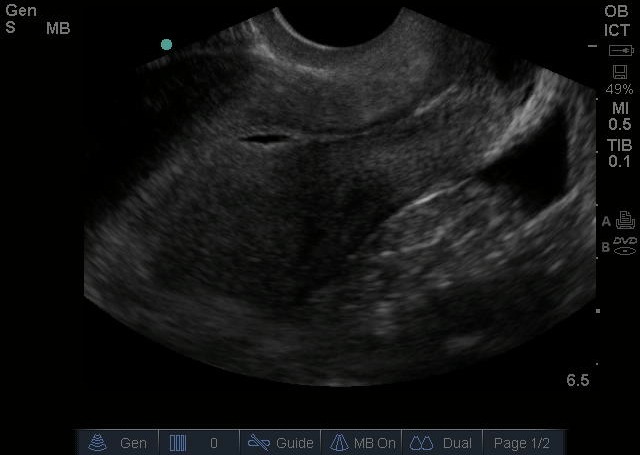

Bild 2: Transvaginaler (TV) Ultraschall des Beckens, ektopische Schwangerschaft, Pseudogestationssack, sagittal, freie Flüssigkeit